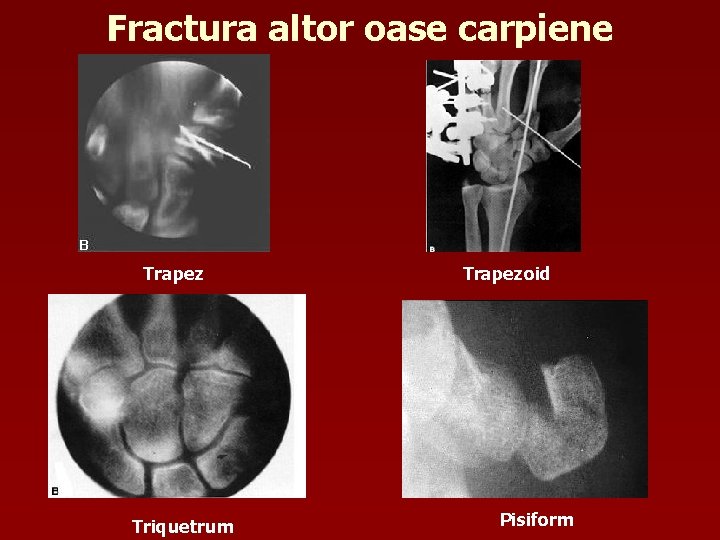

Fractura altor oase carpiene Trapez Triquetrum Trapezoid Pisiform